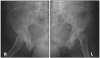

4) Roof arc angle : Acetabular fx에서 정상 상부의 정도를 평가하는 방법

대퇴골두 중심에서 수직선과 비구 골절선과 비구 중심을 연결한 선 사이의 각도로 측정합니다.

전후면 사진에서 내측 roof arc angle을, iliac wing view에서 전방 roof arc angle을, obturator foramen view에서 후방 roof arc angle을 측정합니다.